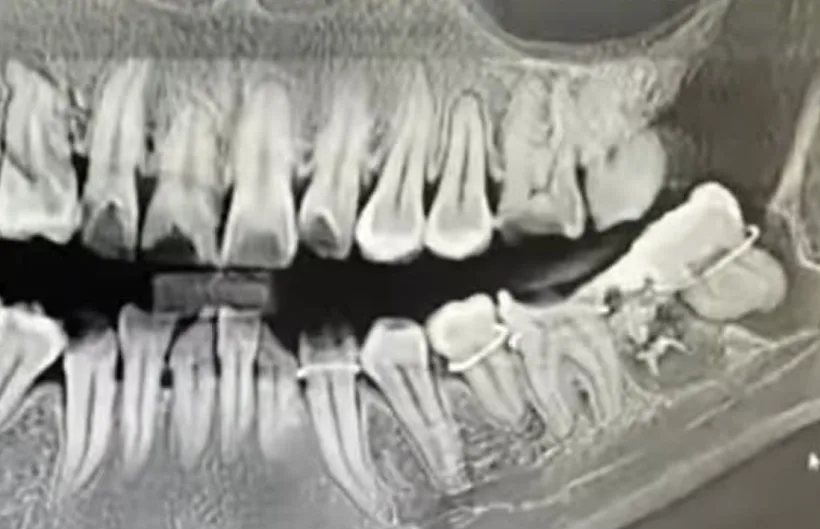

סין: אישה בת 34 מאנחווי, פנתה למרפאת השיניים בבית החולים העירוני אנקינג על מנת לעבור הליך עקירת שן בינה. אלא שלמרבה הצער והאימה, רופא השיניים ביצע את ההליך בצורה שגויה והסיר בטעות שן בריאה.

אחיה של האישה, התראיין לתקשורת המקומית וסיפר כי הרופא ניסה לתקן את הטעות שלו ולהחזיר את השן ולקבע אותה עם חוט ברזל. "הניתוח ערך שעה וחצי ללא חומרי הרדמה. אחותי סבלה מכאבים", אמר.

האישה דיווחה על המרפאה לרשויות מספר פעמים, אך לדברי אחיה, לא ננקטו שום פעולות. היא פרסמה סרטון ברשתות החברתיות בו היא האשימה את בית החולים ברשלנות, וטענה כי הרישומים הרפואיים שלה שונו על מנת לכסות על הטעות. היא טענה שבית החולים לחץ עליה למחוק את הסרטון, והציע לה השתלת שיניים כפיצוי.